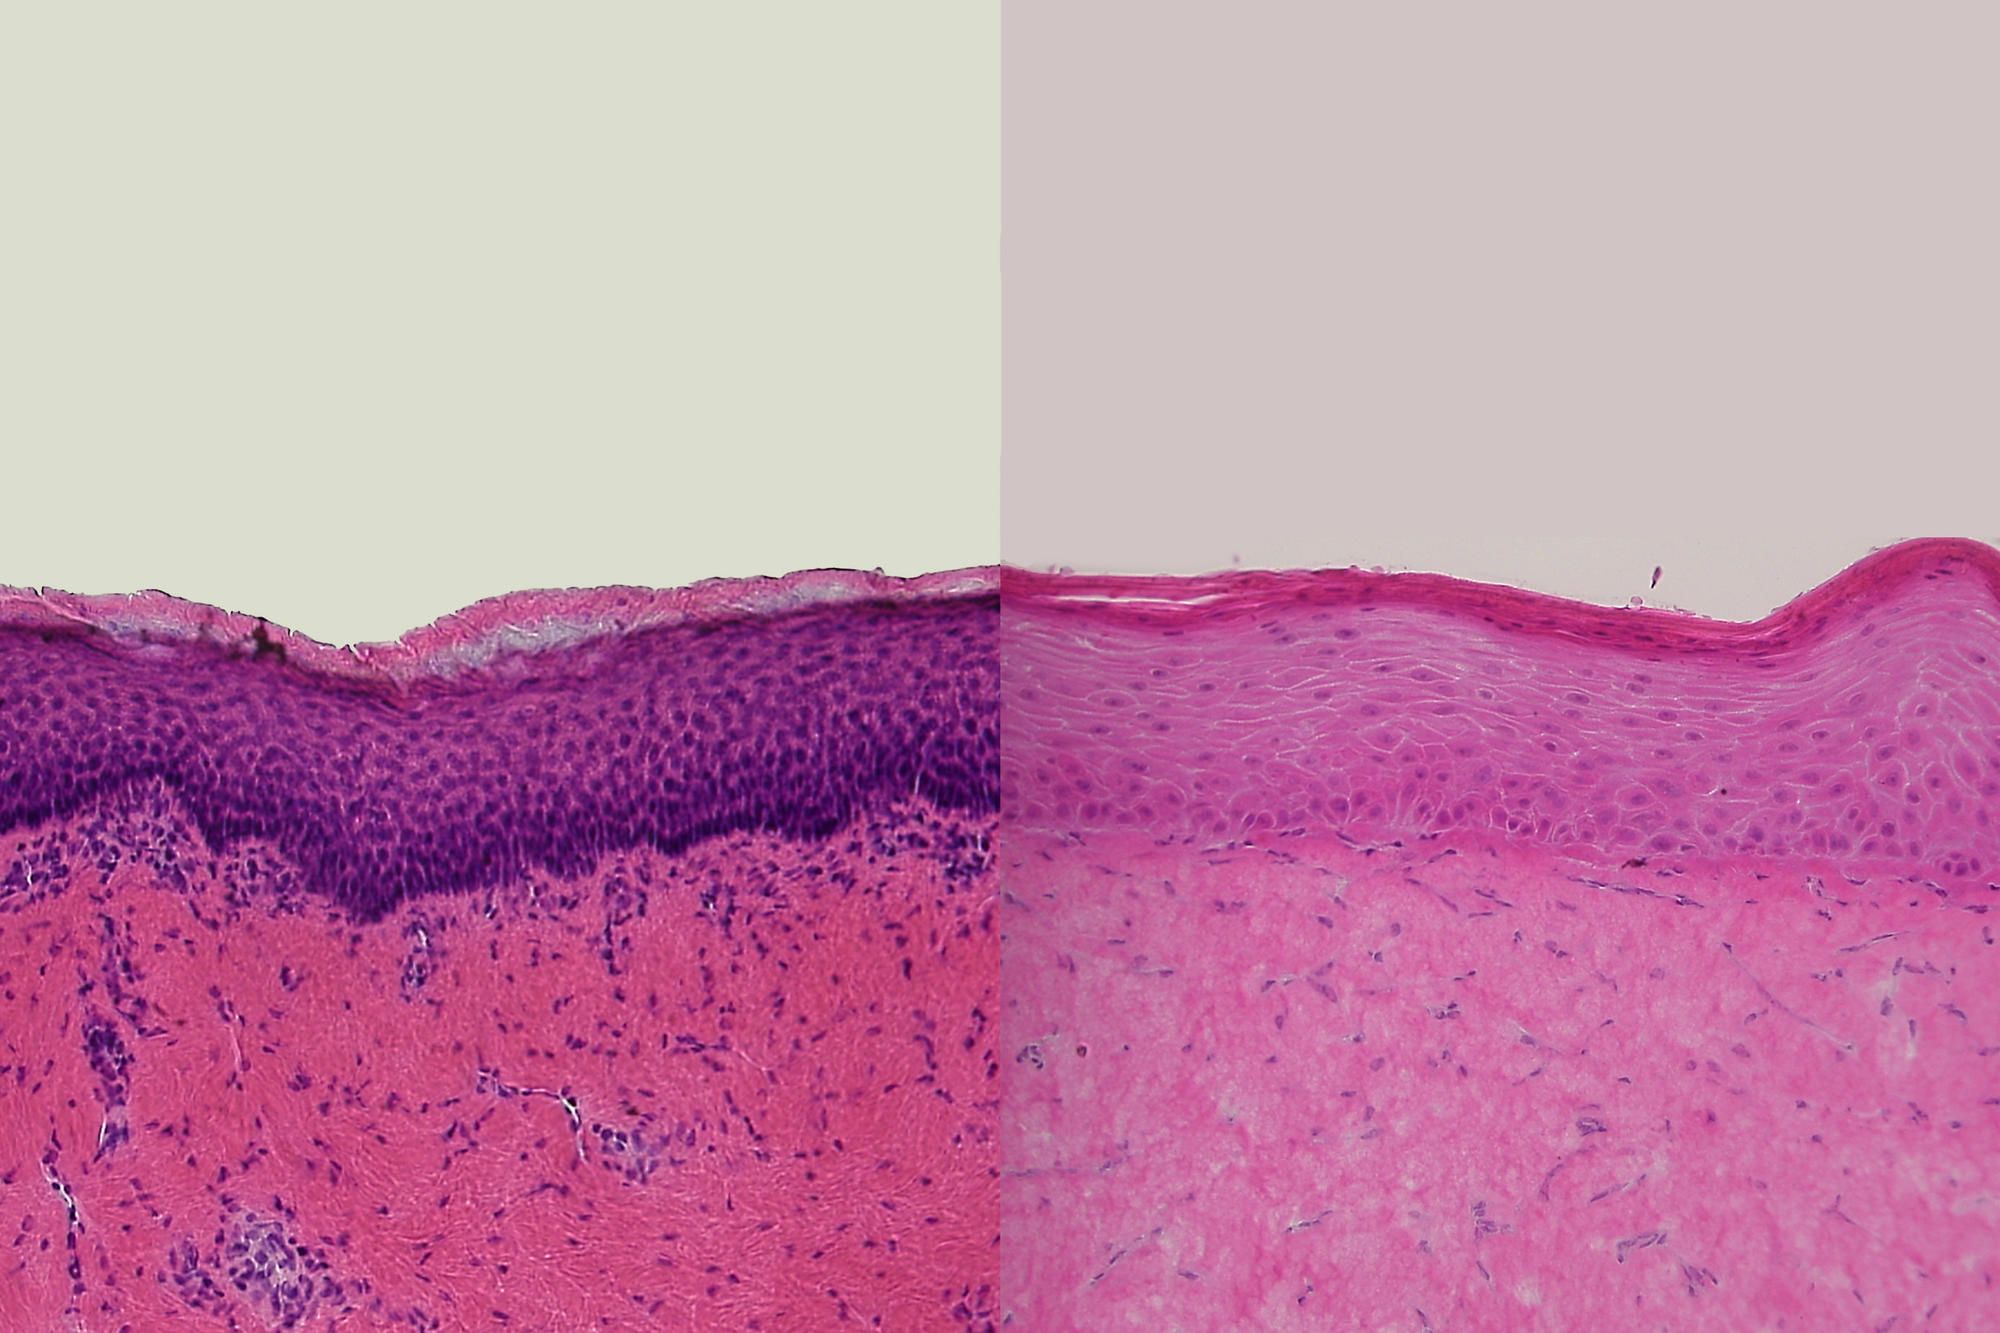

Die Querschnitte durch Humanhaut ex vivo (links) und durch rekonstruierte Humanhaut (rechts) zeigen große Ähnlichkeiten und sind Ausgangspunkt für die Nutzung von rekonstruierter Humanhaut in der Erforschung von Hautkrankheiten.

Bildquelle: Christian Hausmann